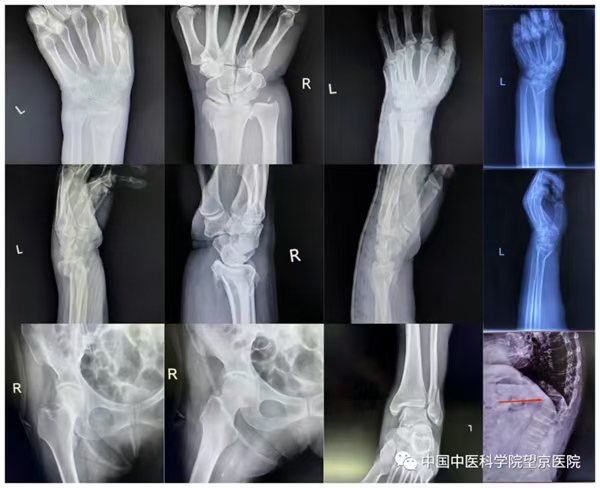

骨折的好发部位

桡骨远端骨折 :多因摔倒时手撑地,力量经手腕传导至前臂所致。骨折后腕部及前臂会肿胀、疼痛,局部畸形,是滑倒摔伤中常见的骨折类型,尤其多见于中老年人。